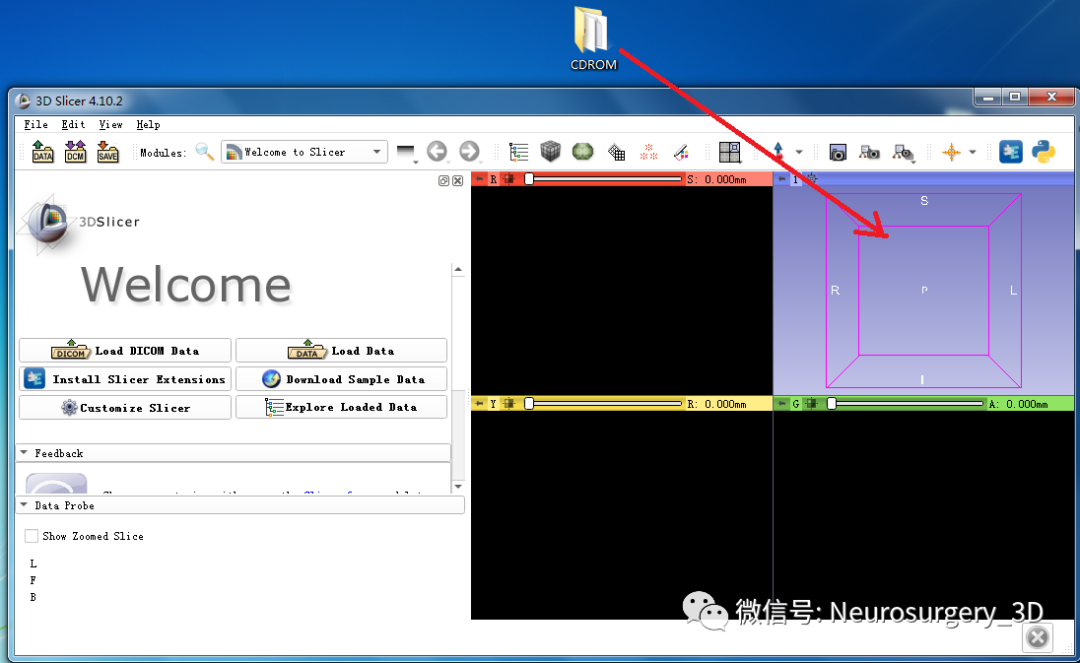

1、在电脑端打开3D-Slicer界面

2、把准备好的患者DICOM数据直接拉入3D-Slicer界面